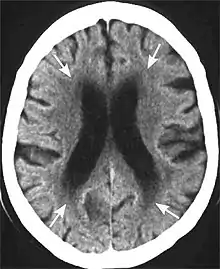

Leukoaraiosis is a particular abnormal change in appearance of white matter near the lateral ventricles. It is often seen in aged individuals, but sometimes in young adults.[1][2] On MRI, leukoaraiosis changes appear as white matter hyperintensities (WMHs) in T2 FLAIR images.[3][4] On CT scans, leukoaraiosis appears as hypodense periventricular white-matter lesions.[5]

These white matter changes are also commonly referred to as periventricular white matter disease, or white matter hyperintensities (WMH), due to their bright white appearance on T2 MRI scans. Many patients can have leukoaraiosis without any associated clinical abnormality. However, underlying vascular mechanisms are suspected to be the cause of the imaging findings. Hypertension, smoking, diabetes,[3] hyperhomocysteinemia, and heart diseases are all risk factors for leukoaraiosis.